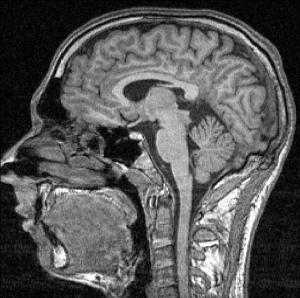

Ob gadoliniumhaltige MRT-Kontrastmittel unbedenklich sind, darüber wird kontrovers diskutiert. Trotz Ablagerungen im Gehirn gibt es keinen Hinweis auf negative Folgen. Ärzten wird dennoch empfohlen, mit möglichst niedrigen Dosen zu arbeiten. Mehr lesen…